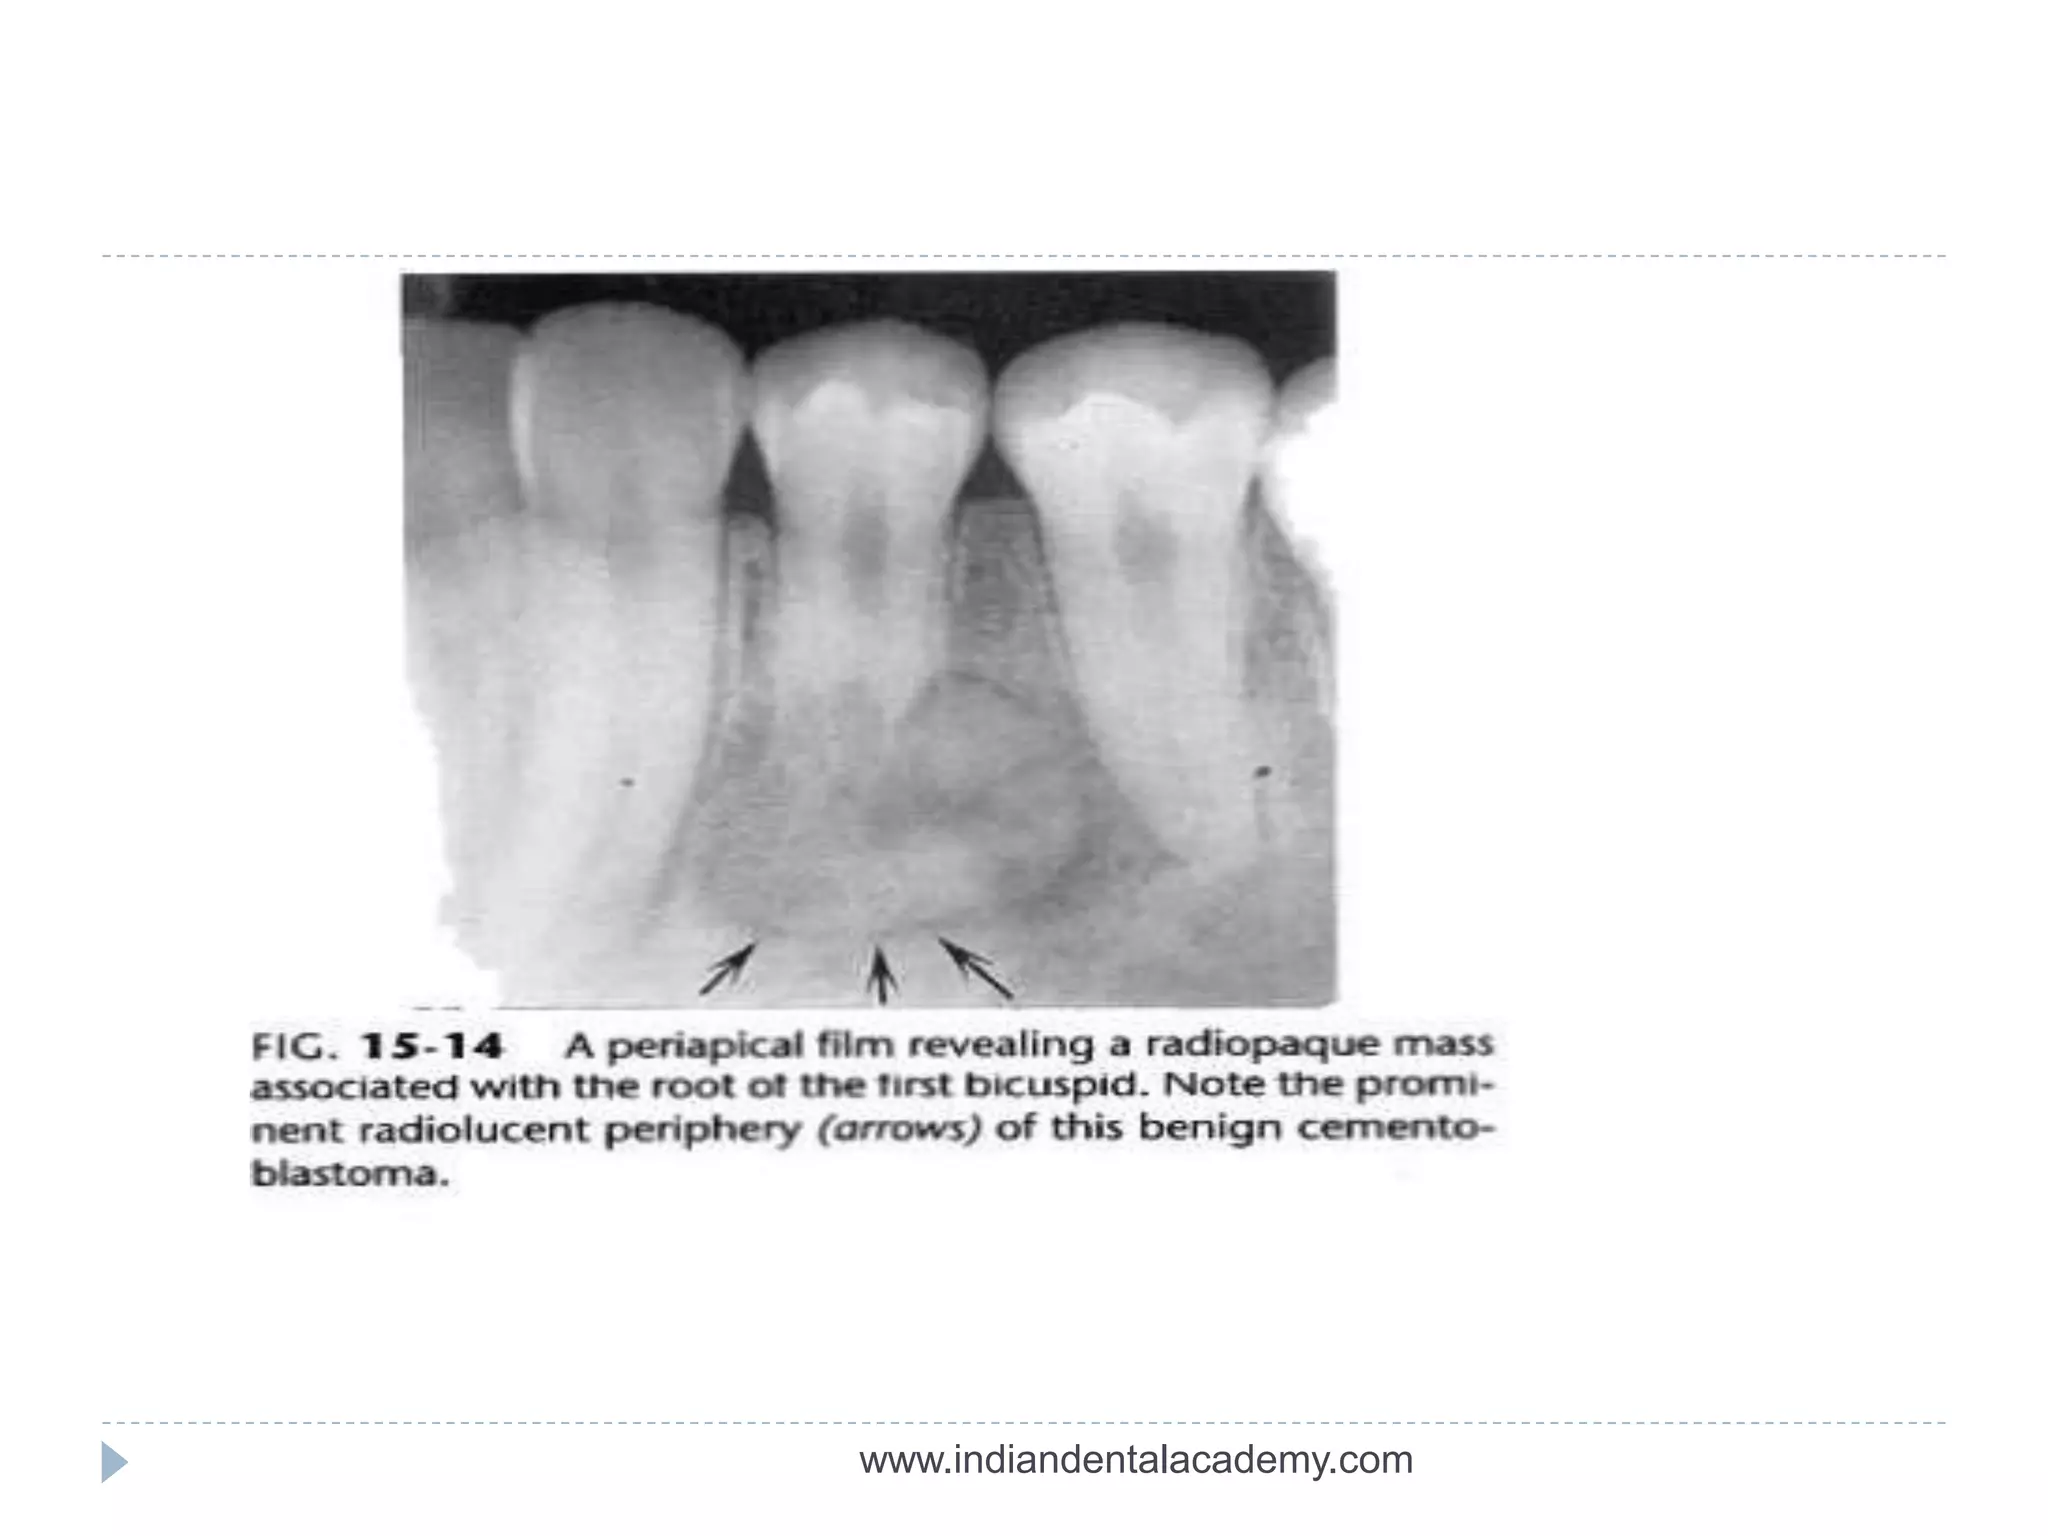

 WELL OR POORLY DEMARCATED

 Radiolucent(periphery)+ corticated

Odontoma , cementoblastoma